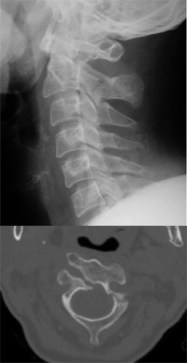

Las figuras 1, 2 y 3 ilustran ejemplos de signo, hallazgo y patrón.

Figura 1. Signo de la C2 ancha. Consiste en un aumento de la distancia entre el margen anterior y el posterior de C2 en relación con C3. Corresponde a una fractura oblicua del cuerpo vertebral con desplazamiento de un fragmento sobre el otro, dando la apariencia de un agrandamiento del diámetro anteroposterior. Según la oblicuidad de la línea de fractura, ésta puede no verse en la radiografía.